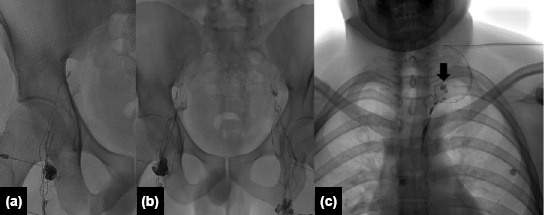

Methods: Between April 2018 and July 2022, eight patients who underwent IL for CL following thyroid and thoraco-abdominal surgeries were included in this retrospective study. Among these eight patients, six underwent bilateral total thyroidectomy, one underwent lobectomy of the lung, and one underwent total abdominal hysterectomy with bilateral salpingo-oophorectomy. Prior to the procedure, thoracic duct ligation was attempted in one patient. Lymphangiographic findings, technical and clinical success rates, and complications were analyzed. Technical success was defined as the successful ultrasound-guided puncture of an inguinal lymph node and the opacification of the lymphatic system in the pelvis and abdomen by fluoroscopy. Clinical success was defined as a progressively decreasing drain output, culminating in the cessation of output within one week after the procedure.

Results: Technical and clinical success was achieved in all patients. On lymphangiography, ethiodized oil leakage near the surgical bed was identified in seven of the eight patients. The median time from the procedure to drain removal was three days (range: 1-6 days) for patients who underwent surgical drainage. No recurrence of CL, chylothorax, or chylous ascites was observed during the follow-up period (range: 21-73 months; median: 38 months).